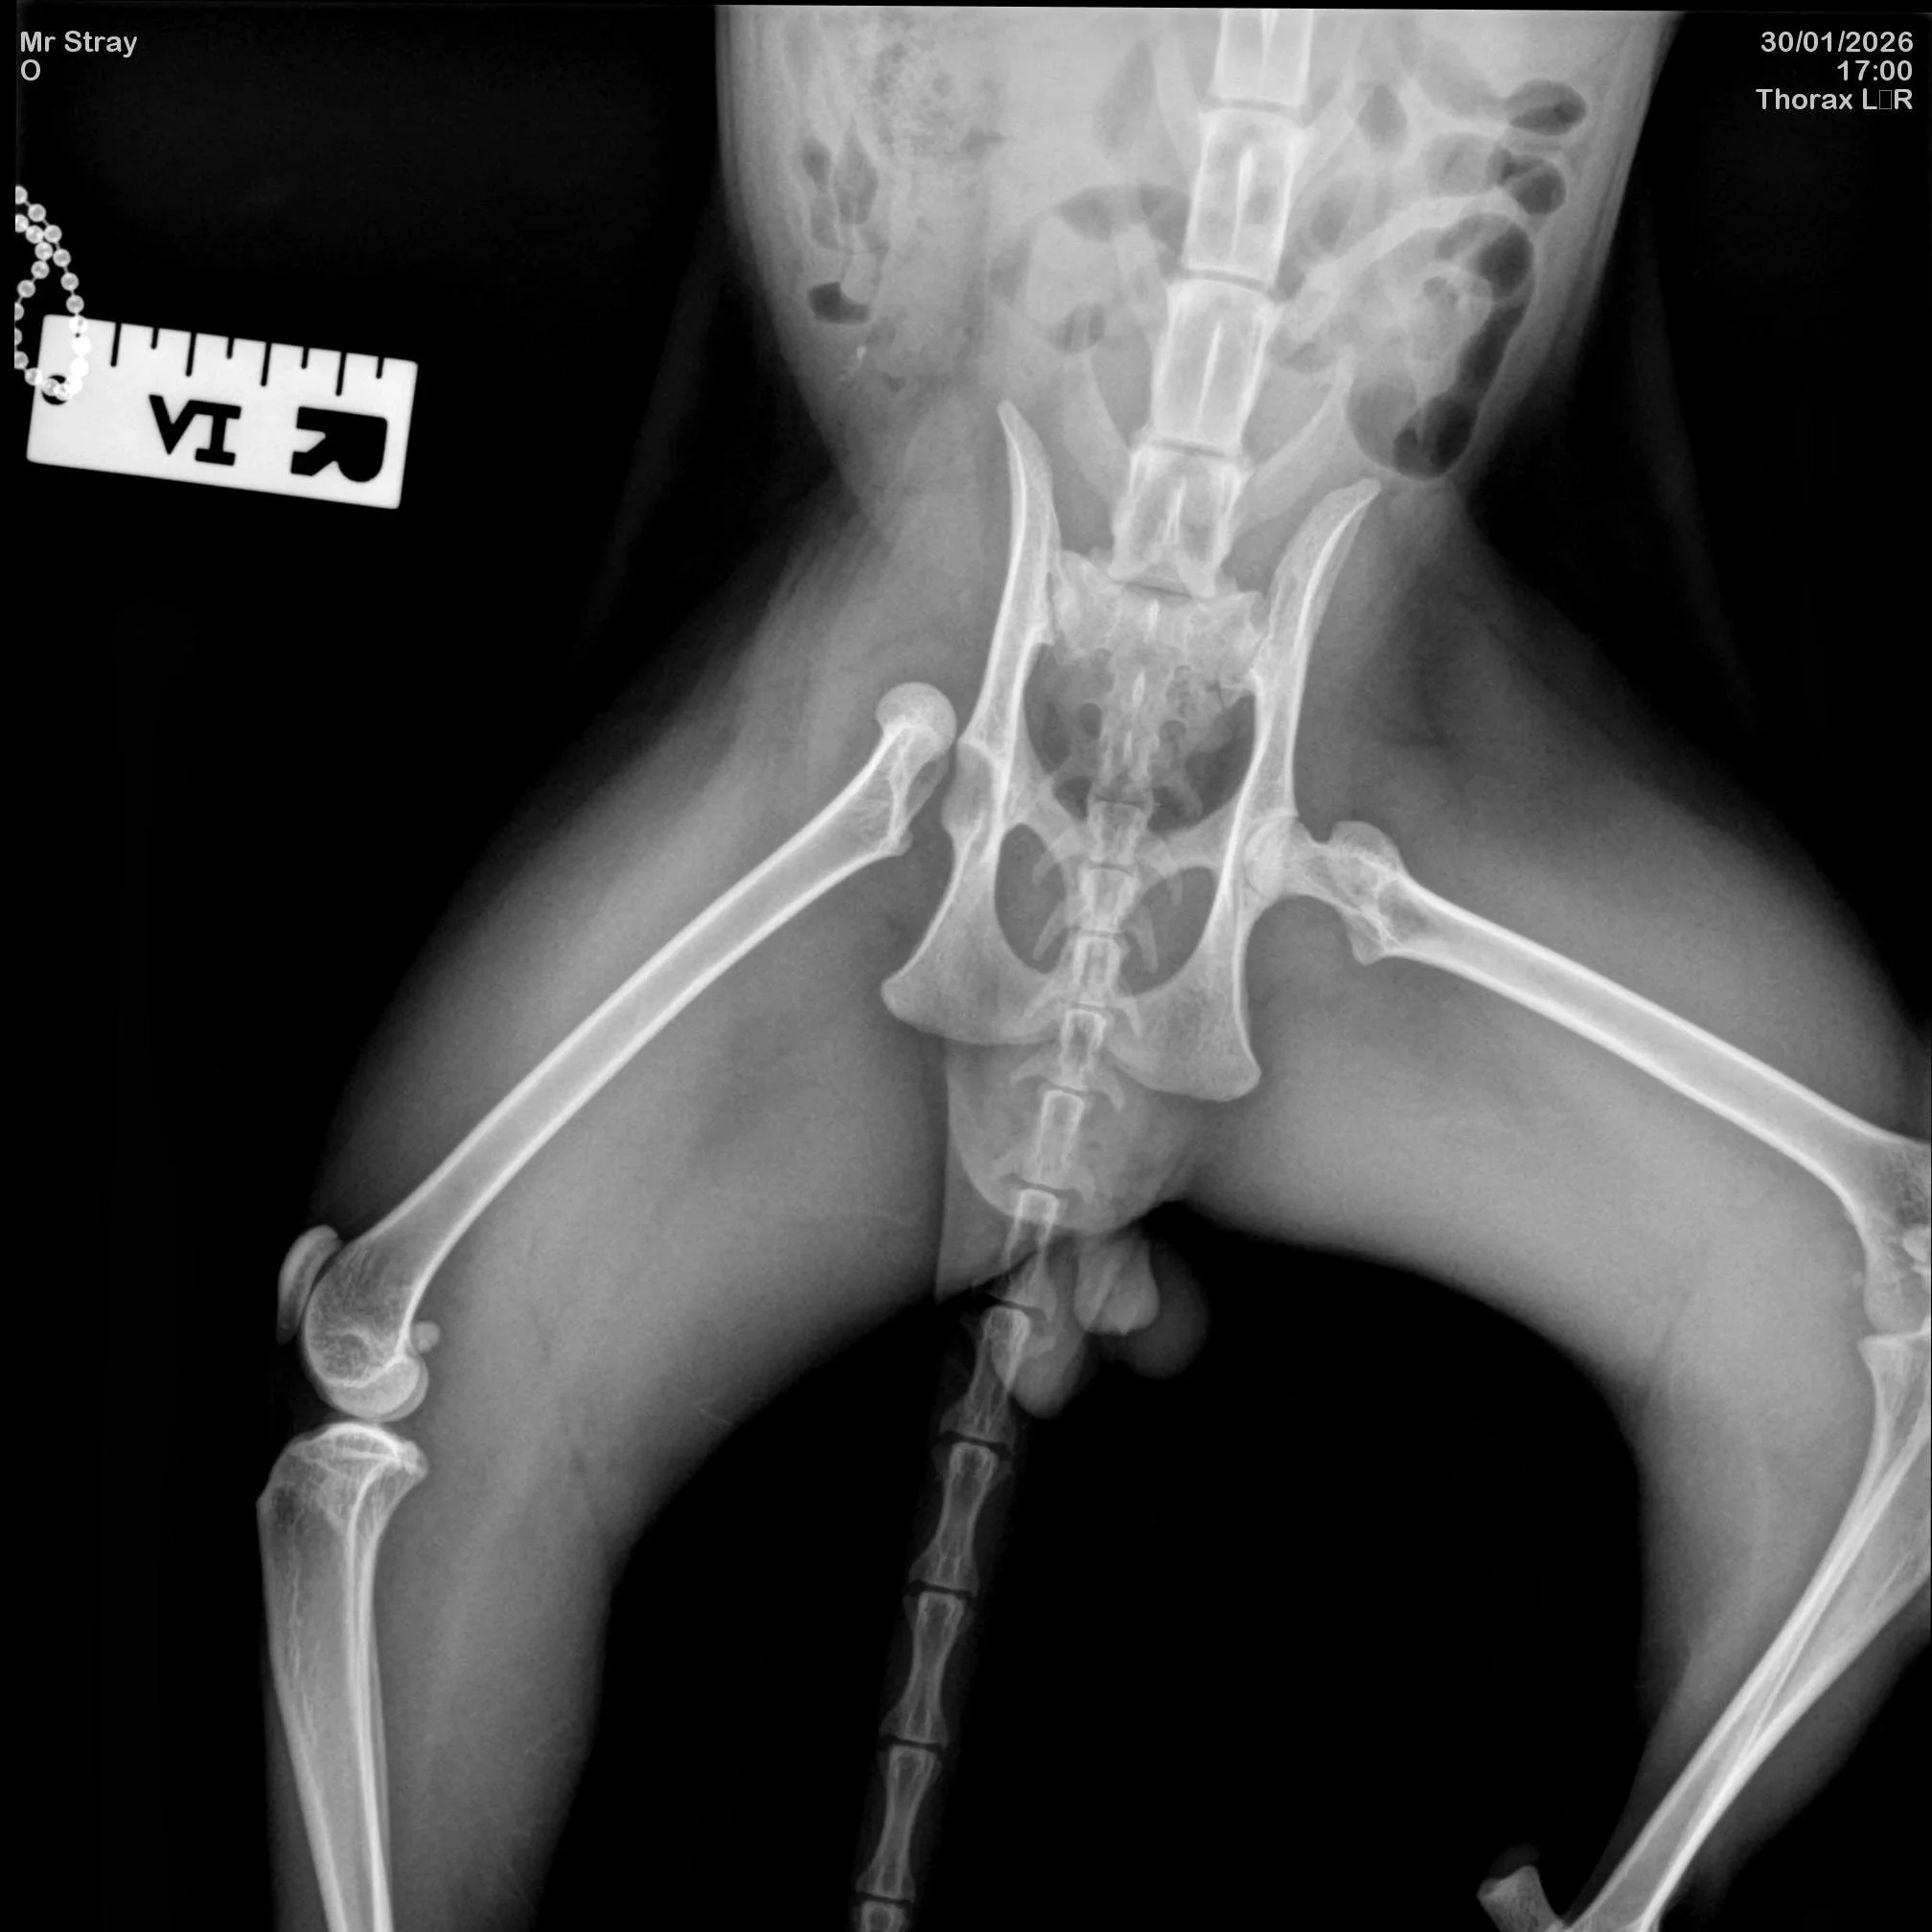

An x-ray image showing the dislocated femur

Elvis, the three-year-old male cat, described by rescuers as gentle and resilient despite his ordeal, was discovered after being struck by a vehicle and left with a dislocated femur. With no registered owner and no one to cover his veterinary costs, his future now depends entirely on charitable support.